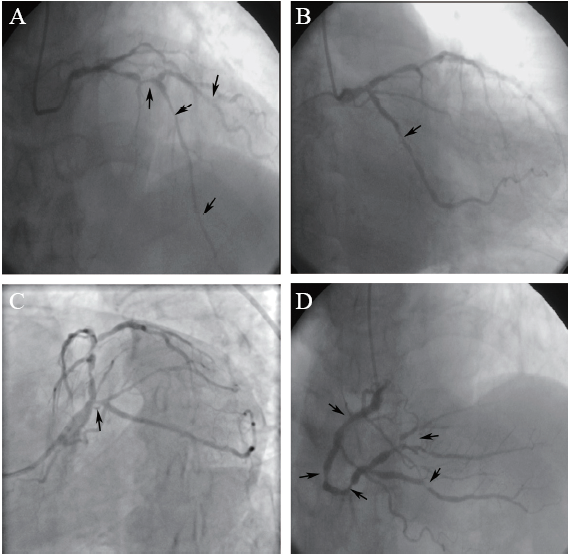

图1 一例NSTEMI患者术前CAG图

A:右肩位显示前降支近段可见约90%狭窄,中段可见约80%狭窄,远段可见约90%弥漫性狭窄,第一对角支近段可见约70%狭窄;B:正头位显示回旋支中段可见约90%弥漫性狭窄;C:蜘蛛位显示左主干末端可见约50%狭窄,回旋支开口可见约80%狭窄;D:正头位显示右冠状动脉近段可见约80%狭窄,中段可见约80%狭窄,远段可见约90%狭窄,后降支开口可见约80%狭窄,中段可见约90%狭窄,左室后支近段约90%弥漫性狭窄;箭头所示狭窄处

患者行CAG示左主干+三支病变(图1),SYNTAX评分64分,建议首选冠状动脉搭桥术,患者及家属拒绝冠状动脉搭桥术。患者频繁发作胸痛症状,心肌梗死指标高,冠心病系亟待解决的主要问题,结合患者血小板水平及以后长期双联抗血小板聚集(DAPT)治疗的风险,适宜选择抗血小板治疗时间短、出血风险低的策略,因此首选药物球囊扩张术。术前先加用双联抗血小板聚集药物(阿司匹林100 mg/d+氯吡格雷75 mg/d),同时应用升血小板聚集药物(重组人血小板生成素+重组人IL-11皮下注射),并备血及血小板,治疗3 d后复查血常规提示血小板较前无明显下降。于2020年1月13日在局部麻醉下分别对右冠状动脉及回旋支病变行药物球囊扩张术,术中先对病变充分预扩张,右冠状动脉先后应用3.0 mm×26.0 mm、3.0 mm×26.0 mm、3.5 mm×26.0 mm的药物球囊,回旋支先后应用2.75 mm×26.00 mm、3.0 mm×17.0 mm的药物球囊,对病变进行扩张,术后可见右冠状动脉、回旋支病变程度较前明显减轻(图2、3),紫杉醇药物球囊均由德国贝朗公司生产。